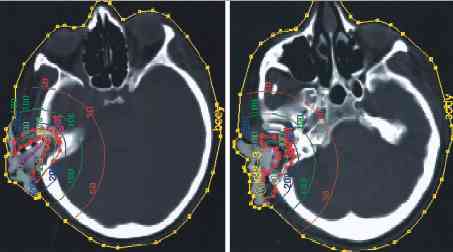

ear_ct_plan.gif (6373 bytes) small_outer.jpg (9938 bytes) ear_ct_plan.jpg (12453 bytes)

For 3D CT-based EBRT of EAC and middle ear, we established target volume concepts based on anatomical findings. Rouvi้re  describes the lymphatic capillary network in the EAC continuous with the network of the auricle and the tympanic membrane. Three zones with different lymphatic drainage are found in the ear canal: the anterior aspect which drains into the intraglandular and preauricular nodes, the inferior portion of the canal, which drains inwardly, following the canal to terminate in deep intraglandular parotideal or infraauricular nodes, and the posterior aspect of the canal takes a deep course, skirting the origin of the sternomastoid muscle to the nodes lying there. The capillary network of the tympanic membrane is continuous with that of the external auditory canal and the mucosal aspect of the middle ear. Thus, we included all possibly involved lymphatic pathways into our target volume as described above. Since carcinomas of the EAC often invade along the perineural pathways , dichotomously far beyond macroscopic extension of disease, they become most difficult to eradicate  We take perineural tumor spread into account when defining target volume. More recently, we integrated the superficial compartment innervated by the ipsilateral facial nerve into the clinical target volume  in these cases of perineural infiltration of facial nerve. Using this target volume concept, we achieved local control for a period of 2.4–3.3 years in postoperative situation.